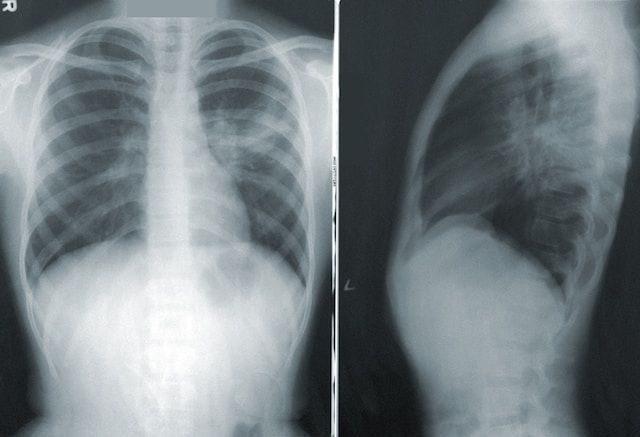

A new study published in Nature reveals that air pollution, traditional herbal remedies, and environmental contaminants may be contributing to lung cancer in people who have never smoked. Researchers analyzed lung tumors from 871 never-smokers across 28 regions and discovered specific DNA mutation patterns tied to high pollution exposure—many similar to those caused by tobacco use.